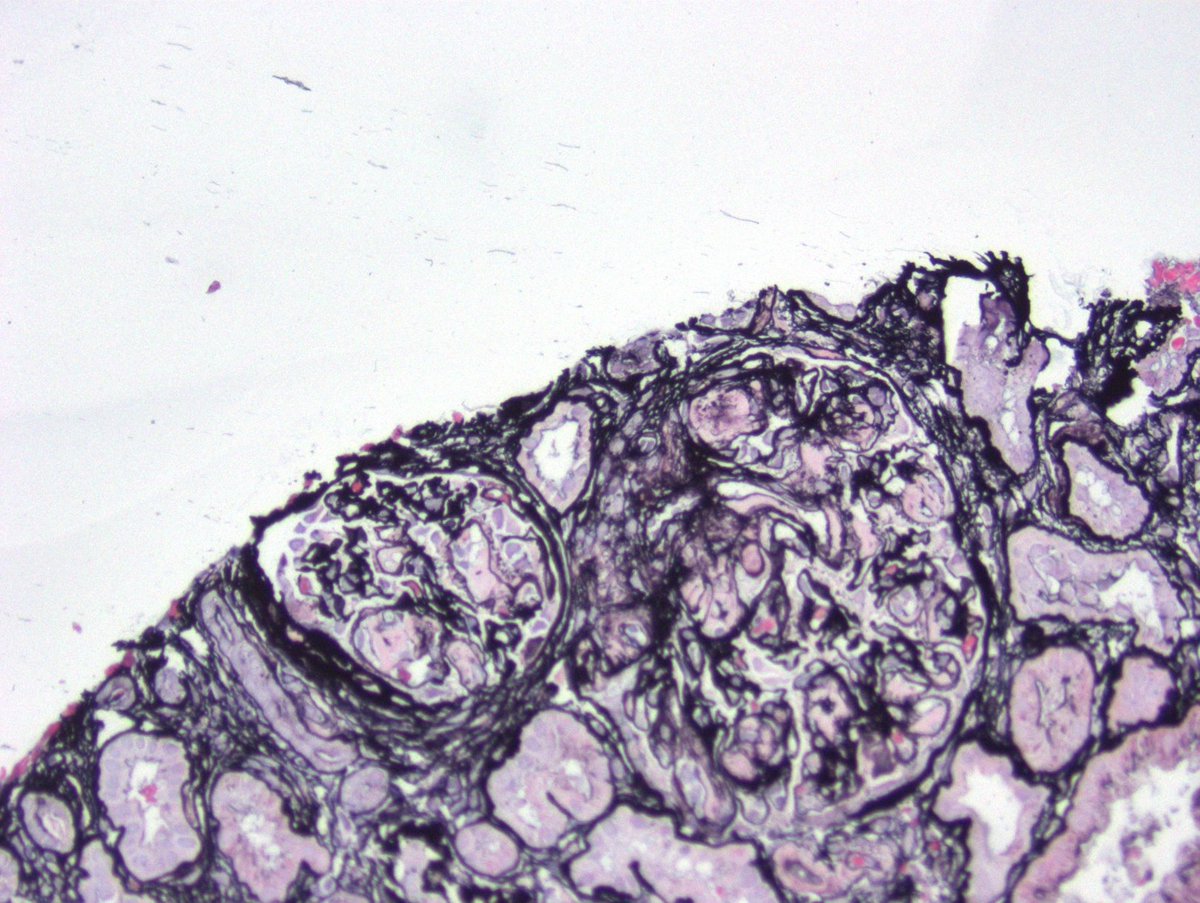

Long weekend often brings urgent cases. Here is one that was STATed, ended up showing anti-GBM GN. Diffuse crescents (nearly 100%). Linear IgG. #RenalPath